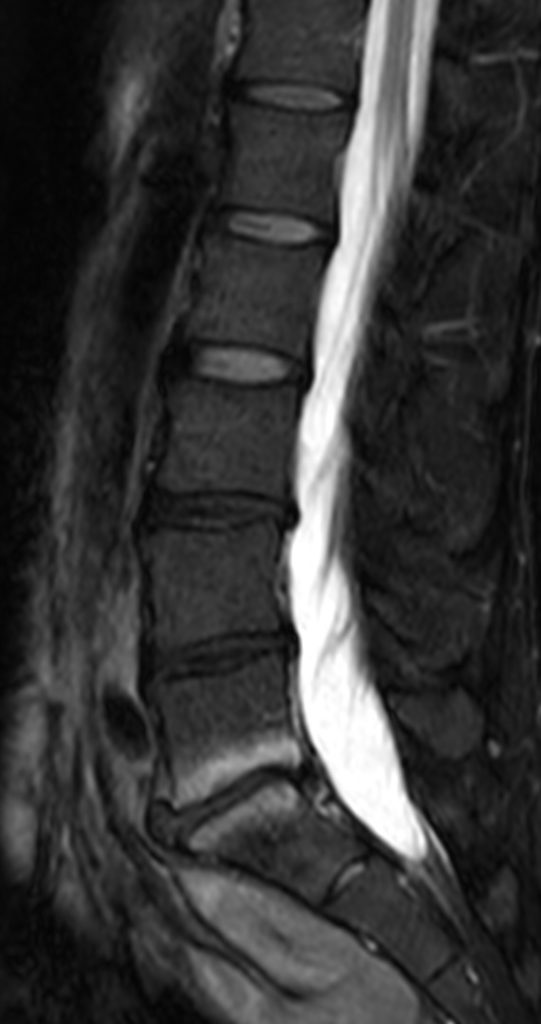

Exemple de remaniement inflammatoire Modic I en L5-S1

Modic fait référence à un médecin à l'origine d'une classification parue à la fin des années 1980. Cette classification décrit des anomalies de signal IRM des corps vertébraux secondaire à une discopathie.

Le Modic 1 correspond à des remaniements inflammatoires et donc douloureux des plateaux vertébraux. Encore une fois, ce n'est pas la discopathie qui est responsable de la douleur mais elle est à l'origine des remaniements Modic.

Plus les remaniements Modic 1 sont étendus aux corps vertébraux, plus la douleur est importante.